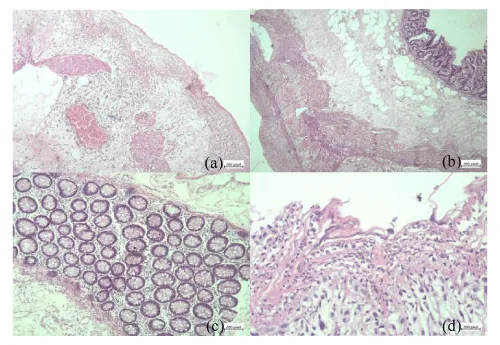

Right hemicolectomy and peritoneal toileting were done. Drainage tube was inserted. Histology showed mucosal oedema, infiltration with inflammatory cells mainly polymorphs, lymphocytes, few plasma cells and histiocytes. Congested vessels with areas of haemorrhages in the mucosa (Figure 4). Organisms, granuloma, cellular and nuclear atypia are not found.